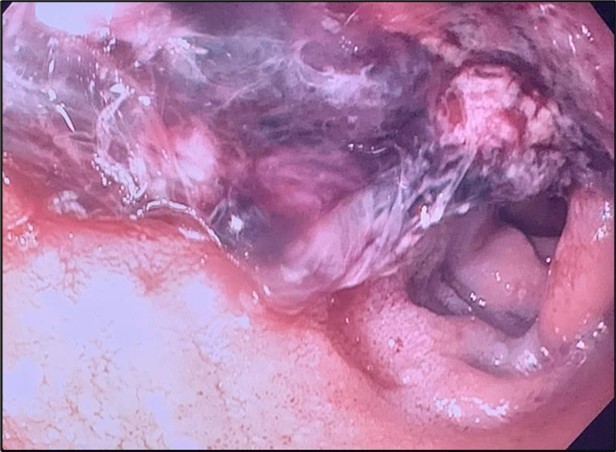

Image 1.Duodenal ulcer with large adherent clot.

A proton pump inhibitor infusion was started, and urgent upper endoscopy showed a 4 cm non-obstructing, deeply cratered duodenal ulcer with a large clot and diffuse oozing (Image 1). Hemostasis was achieved with the use of mineral powder that provides physical compression and promotes clotting. The lesion was not amenable to other forms of treatment given its size. She was subsequently extubated and transferred to the medical floor, where she had recurrence of melena. The patient’s melanotic stools self-resolved, but a continuously increasing alkaline phosphatase was noted, which prompted further workup (Figure 1).